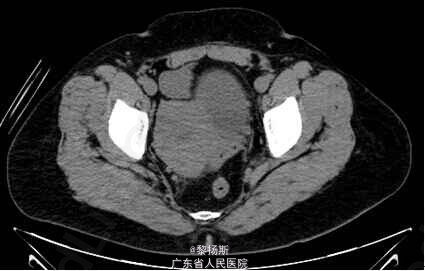

女性,42岁,”发现盆腔包块2年”,无腹痛,无异常阴道流血;自述10年前曾因“盆腔炎” 在外院手术治疗,切除一侧附件,具体不详,有子宫肌瘤病史。

查体:生命体征平稳。腹部可触及包块。影像学:左侧附件区见一囊实性占位,边界清晰,囊性成分较多,增强内可见分隔,囊壁强化明显,并可见强化壁结节。实性成分强化明显。盆腔未见明显肿大淋巴结,未见明显积液。鉴别诊断:卵巢浆液性囊腺癌:也表现为附件囊实性包块,可见分隔,亦可见强化壁结节,鉴别诊断欠困难,有文献称CA125较透明细胞癌升高。病理示:左侧卵巢透明细胞癌。

诊断:左侧卵巢透明细胞癌

原发性卵巢肿瘤分为三种类型,既上皮肿瘤、性索间质肿瘤、生殖细胞肿瘤,卵巢上皮肿瘤依据上皮细胞的类型又分为浆液性癌、粘液性癌、子宫内膜样癌及透明细胞癌。卵巢透明细胞癌是一种起源于苗勒管的卵巢上皮恶性肿瘤,约占卵巢上皮癌的5%,恶性程度高。多发生于成年女性,几乎所有患者诊断时年龄均为25岁以上,临床表现以腹部肿块最常见。透明细胞癌影像上以囊实性肿块多见,并以囊性部分为主,内可见分隔,并可见强化壁结节。实性部分表现为腔内突起,形态不一,乳头或息肉状,部分呈类圆形。肿瘤血供丰富,动脉期明显强化,静脉期及平衡期仍持续强化。难与浆液性囊腺癌鉴别。有文献报导,与浆液性囊腺癌比较,卵巢透明细胞癌具有不同的临床及分子生物学特点:①术前血清CA125值较低,腹腔积液出现几率少,术后残余肿瘤较小。②肿瘤单侧发生,乳头状突起呈分级分支模式。③合并子宫内膜异位症,尽管不特异,也应考虑该肿瘤可能。④免疫组化:Wilms瘤I基因(WT1)和雌激素受体(ER)表达多呈阴性。术前诊断比较困难,确诊主要依靠病理学检查。